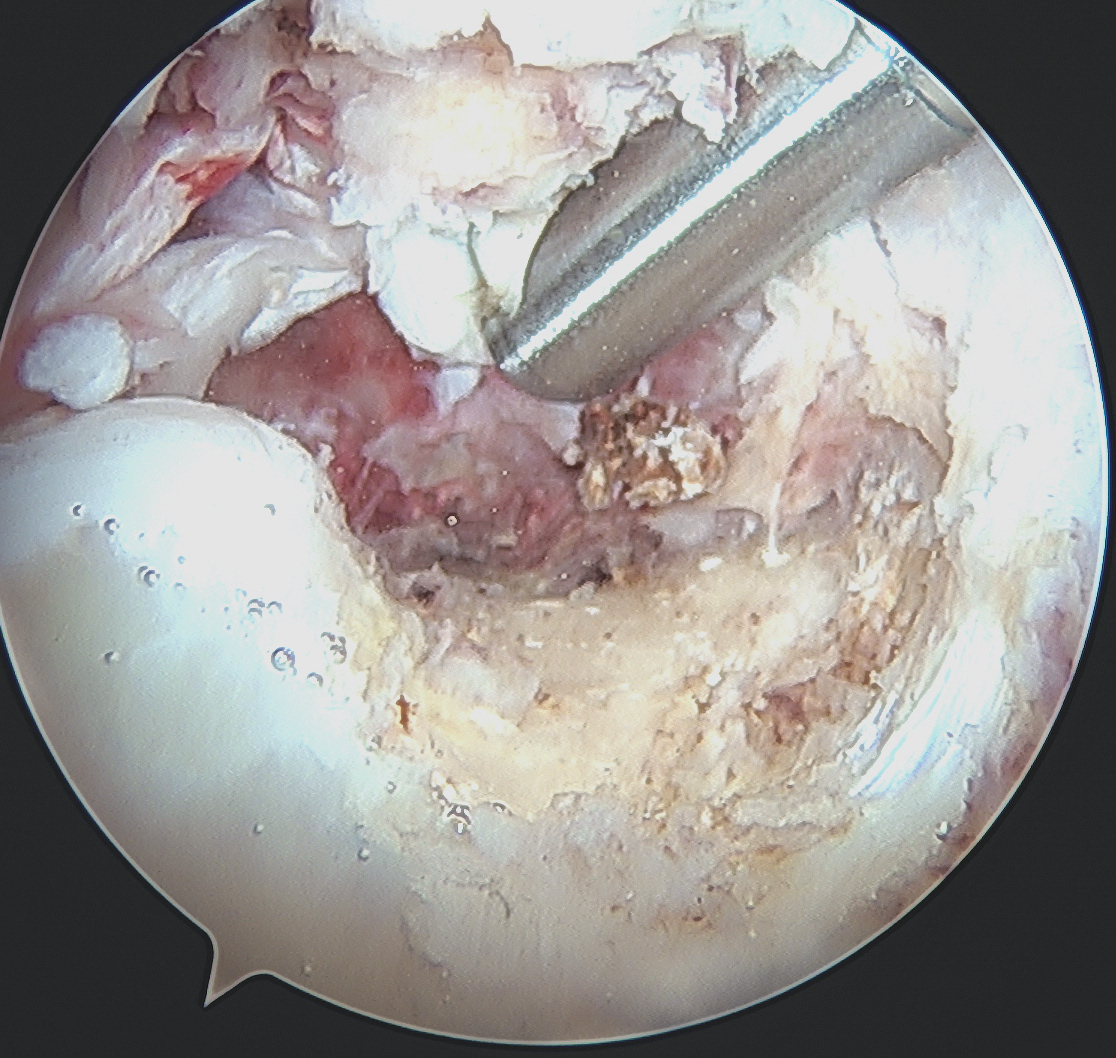

Arthroscopy

Debridement of notch

Place posteromedial cannula

- most common mistake is placing cannula too anterior / inferior

- need to be able to instrument PCL origin

- also allows direct visualisation with camera

Assess / treat meniscus